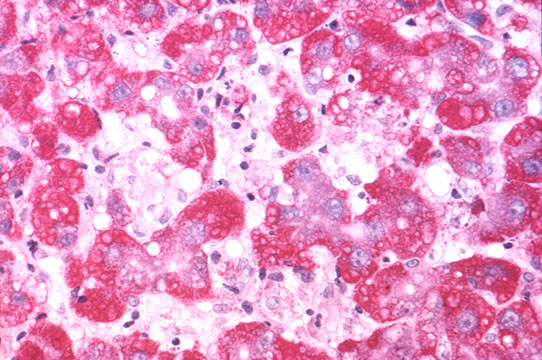

De-glycogenation

Fig 57 - DE-GLYCOGENATION: Injured cells lose their glycogen at very early stages. These same cells are those that release cytoplasmic enzymes in the serum. PAS stain. Glycogen stains red..